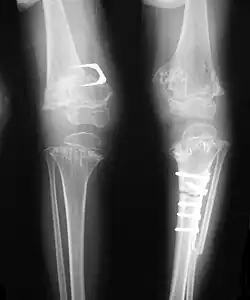

Pseudoachondroplasia. Leg radiographs depicting dysplastic distal femoral and proximal tibial epiphyses, and distal femoral metaphyseal broadening, cupping, irregularities (white arrows) and radiolucent areas especially medially. Note the metaphyseal line of ossification of the proximal tibias (blackarrows) and relative sparing of the tibial shafts. The changes around the knee are known as "rachitic-like changes". Lesions are bilateral and symmetrical.

Skeletal radiography

Accurate assessment of plain radiographic findings remains an important contributor to diagnosis of pseudoachondroplasia. It is noteworthy that vertebral radiographic abnormalities tend to resolve over time. Epiphyseal abnormalities tend to run a progressive course. Patients usually suffer early-onset arthritis of hips and knees. Many unique skeletal radiographic abnormalities of patients with pseudoachondroplasia have been reported in the literature.[2][7][4]

- Together with rhizomelic limb shortening, the presence of epiphyseal-metaphyseal changes of the long bones is a distinctive radiologic feature of pseudoachondroplasia.

- Dysplastic/hypoplastic epiphyses especially of shoulders and around the knees.

- Metaphyseal broadening, irregularity and metaphyseal line of ossification. These abnormalities that are typically encountered in proximal humerus and around the knees are collectively known as “rachitic-like changes”.

- Radiographic lesions of the appendicular skeleton are typically bilateral and symmetric.